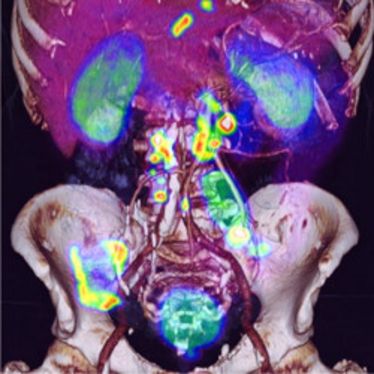

"Dosimetrie bei Innovativen zielgerichteten Tumortherapien in der Nuklearmedizin" (Fortbildung)

"Dosimetrie bei Innovativen zielgerichteten Tumortherapien in der Nuklearmedizin" (Fortbildung)